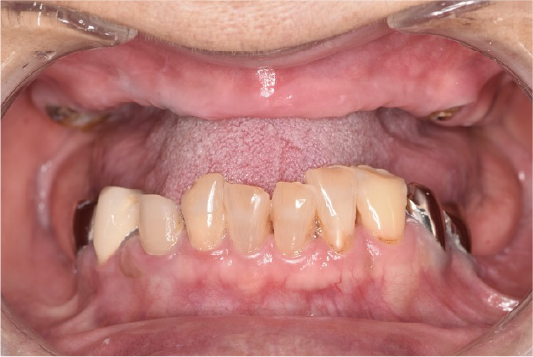

CASE01

■ 治療内容

上下顎All-on-4インプラント治療

■ 治療費用

7,438,000円(税込)

■ 治療期間

約10ヶ月

■ リスク

治療後の腫れや出血、またメンテナンスを怠ることで周囲炎のリスクあります。